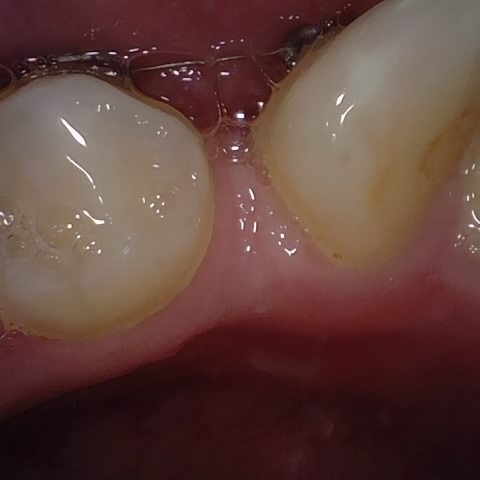

Annotated as "Good"